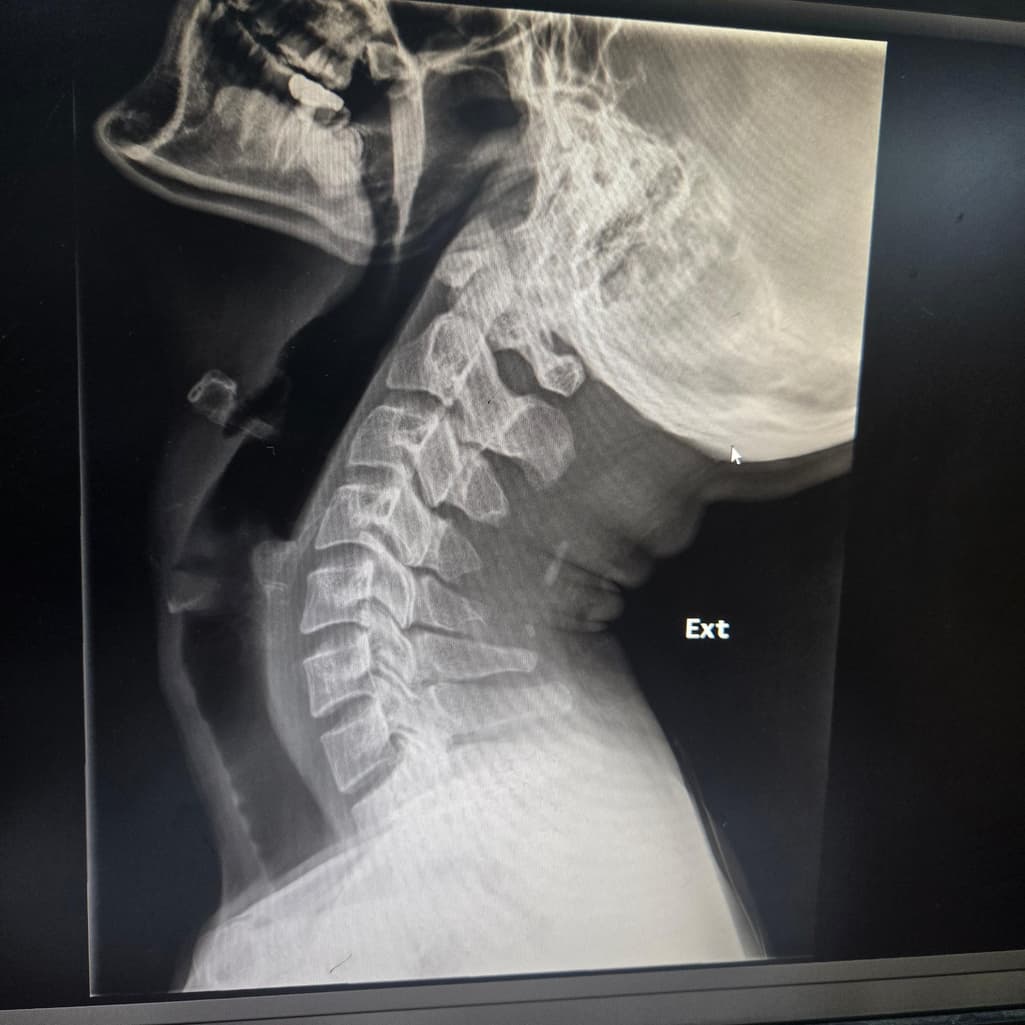

3달째 어지럼증과 경추1,2번쪽과 후두가 베개에 눌리거나 고개를 굽히면 눈도 울렁거리고 맥박도 느껴져요Xray사진인데 경추불안정증이 있나요? 부탁드립니다..경추mri 뇌mri mra 귀 눈 검사는 다 해봤지만 정상입니다.심리쪽 약도 먹었지만 변동없습니다.목 뻐근함과 같이 어지럼증이 왔습니다. 자고일어난후

경추불안정성의 경우 환자분의 경우 C1, C2 사이 거리 혹은 각도를 측정을 해야 합니다.

엑스레이 사진상 flexion과 extension에서 차이는 나지만 그것을 정량적으로 측정을 하기 위해서는

실제 엑스레이 사진으로 평가를 해야 합니다.